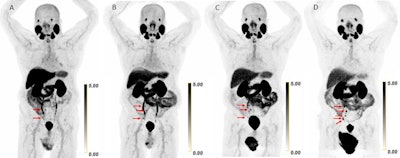

Scans in a 73-year-old man with biochemically recurrent prostate cancer (prostate-specific antigen level of 0.5 ng/mL) who underwent PET/CT with 9.4 mCi of F-18 piflufolastat and a second PET/CT examination with 8.1 mCi of copper 61-NODAGA (1,4,7-triazacyclononane,1-glutaric acid-4,7-acetic acid)–prostate-specific membrane antigen for imaging and therapy (Cu-61 PSMA I&T) 24 days apart, with no intervening therapy. Maximum intensity projection (MIP) images obtained (A) 1 hour after F-18 piflufolastat administration and (B) 1, (C) 2, and (D) 4 hours after Cu-61 PSMA I&T administration are shown. Physiologic uptake is seen in the lacrimal glands, salivary glands, liver, spleen, kidneys, ureters, and bladder. Pathologic uptake in pelvic nodal metastases is labeled with arrows. The F-18 piflufolastat PET/CT MIP image reveals two avid pelvic nodal metastases (arrows). Cu-61 PSMA I&T PET/CT scans demonstrate three avid pelvic nodal metastases on 1-hour and 2-hour images (arrows); five avid pelvic nodal metastases were suspected on the 4-hour image (arrows).Scans in a 73-year-old man with biochemically recurrent prostate cancer (prostate-specific antigen level of 0.5 ng/mL) who underwent PET/CT with 9.4 mCi of F-18 piflufolastat and a second PET/CT examination with 8.1 mCi of copper 61-NODAGA (1,4,7-triazacyclononane,1-glutaric acid-4,7-acetic acid)–prostate-specific membrane antigen for imaging and therapy (Cu-61 PSMA I&T) 24 days apart, with no intervening therapy. Maximum intensity projection (MIP) images obtained (A) 1 hour after F-18 piflufolastat administration and (B) 1, (C) 2, and (D) 4 hours after Cu-61 PSMA I&T administration are shown. Physiologic uptake is seen in the lacrimal glands, salivary glands, liver, spleen, kidneys, ureters, and bladder. Pathologic uptake in pelvic nodal metastases is labeled with arrows. The F-18 piflufolastat PET/CT MIP image reveals two avid pelvic nodal metastases (arrows). Cu-61 PSMA I&T PET/CT scans demonstrate three avid pelvic nodal metastases on 1-hour and 2-hour images (arrows); five avid pelvic nodal metastases were suspected on the 4-hour image (arrows).RSNA